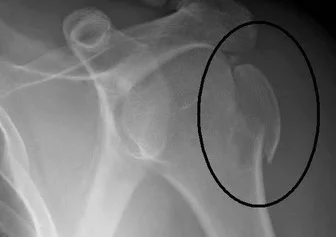

Greater Tuberosity

- Provides attachment to:

- Supraspinatus, infraspinatus, Teres Minor

- Management:

- Minimally/non displaced:

- conservative Sling

- Severely displaced: internal fixation

- By screws / tension band / plate

- To regain function of rotator cuff